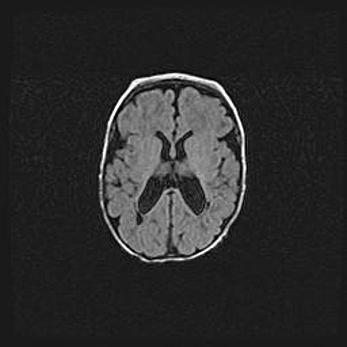

Открытая гидроцефалия.

Возраст: 9 месяцев 12 дней

Вес: 6800 г

Пол: мужской

Окружность головы: 41,5 см

Срок гестации: 28 недель

Гидроцефалия головного мозга у новорожденных имеет характерный признак: опережающий рост окружности головы приводит к визуально хорошо определяемой гидроцефальной форме сильно увеличенного в объёме черепа. Детские неврологи определяют следующие симптомы гидроцефалии у грудничков: выбухающий напряжённый родничок, частое запрокидывание головы, смещение глазных яблок к низу.